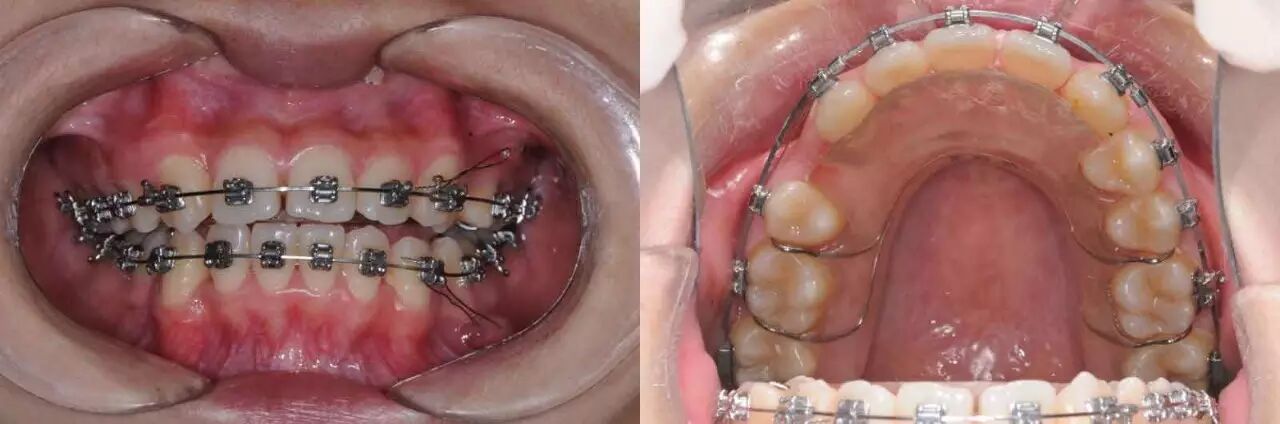

第一种最常见的就是打摇椅,看情况来调整摇椅的大小,没有反应就加大摇椅,直到咬合打开,粘7之后的摇椅更易打开咬合。

第二种可以借助多用途弓之类的压低辅弓,在排齐前牙的同时压低前牙。

第三种就是依靠在前牙牙槽骨里植入微种植钉,依靠绝对支抗来压低前牙。

其实临床上,牙性深覆合与骨性深覆合往往没有那么大的界限,一个患者可能或多或少同时存在部分骨性因素与牙性因素。所以这些方法也经常混合使用,以达到用最小代价最快打开咬合的目的。